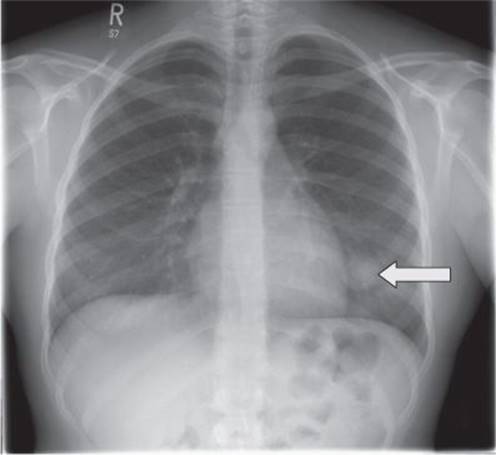

She completed treatment and went onto regular follow-up with chest X-ray and X-ray of the left femur every 3 months. The chest X-ray taken 9 months after completion of treatment is shown in Fig. 24.2.

Fig. 24.2

5. What does the chest X-ray in Fig. 24.2 show?

The chest X-ray shows a solitary round lesion in the left chest close to the heart border. Given the relatively short time since completion of treatment for osteosarcoma, this is likely to represent a lung metastasis.